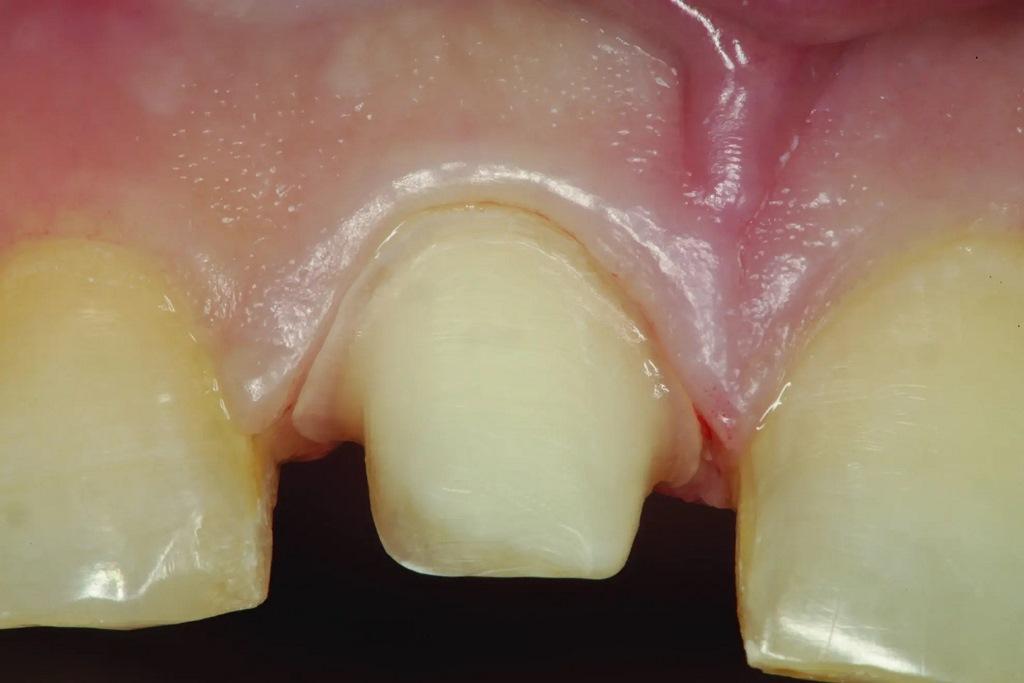

Зуб 11 был подготовлен для установки керамической коронки. Важно подчеркнуть, что подготовка небной поверхности имеет решающее значение. Она должна препарироваться с уменьшением на 1,0–1,5 мм после искривления не препарированной небной поверхности (вогнутости верхнего неба). Это делается для того, чтобы реставрация могла повторять естественный изгиб неба при соответствующей толщине реставрационного материала для придания прочности. Важно помнить, что небная вогнутость верхней челюсти определяется углом возвышения и функциональной оболочкой - обоими окклюзионными факторами, которые необходимо соблюдать при восстановлении передних зубов верхней челюсти. После препарирования (фото 10, 11a-b) можно приступать к изготовлению мастер-оттиска.

Фото 10: Вид снизу на зуб 11 после препарирования и при максимальном смыкании зубов. Следует обратить внимание, что реставрация зуба 41 была необходима для того, чтобы расположить резцовый край и лицевую поверхность в более лингвальном положении, чтобы обеспечить пространство, необходимое для восстановления небной поверхности зуба 11 надлежащей толщины, сохраняя при этом естественную небную вогнутость, частично обусловленную окклюзионными отклонениями.